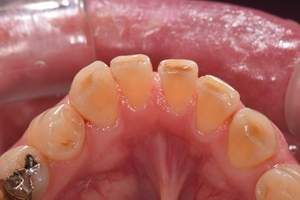

歯石除去

治療前

治療後

| 年齢 | 43歳・男性 |

| 主訴 | 歯石をとりたい |

| 治療内容 | 歯石除去 |

| 治療期間 | 30分 |

| 費用 | 約2,000円 |

| リスク・副作用 | ・歯ぐきの炎症が強いと歯石を取る際に出血することがあります ・処置後に歯がしみることがあります ・歯と歯の間に隙間ができるので、息が漏れ発音しにくいと感じることがあります ・歯ぐきの炎症が軽減すると歯ぐきが引き締まり、歯が長く見えることがあります |